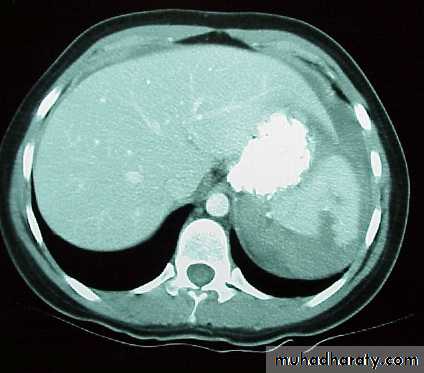

CT Scan

• Replacing DPL.

• 98% sensitive in detecting intraperitoneal bleeding.

• Contrast enhanced CT Scan gives useful anatomical and fuctional information on organs.

• Can identify organ injuries and be used to determine which injuries can be managed conservatively in stable patients.

• Useful in grading solid organ injuries(liver and spleen)..